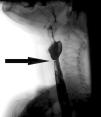

Acta Otorrinolaringológica Española Plummer Vinson syndrome

Plummer Vinson syndrome

Síndrome de Plummer Vinson